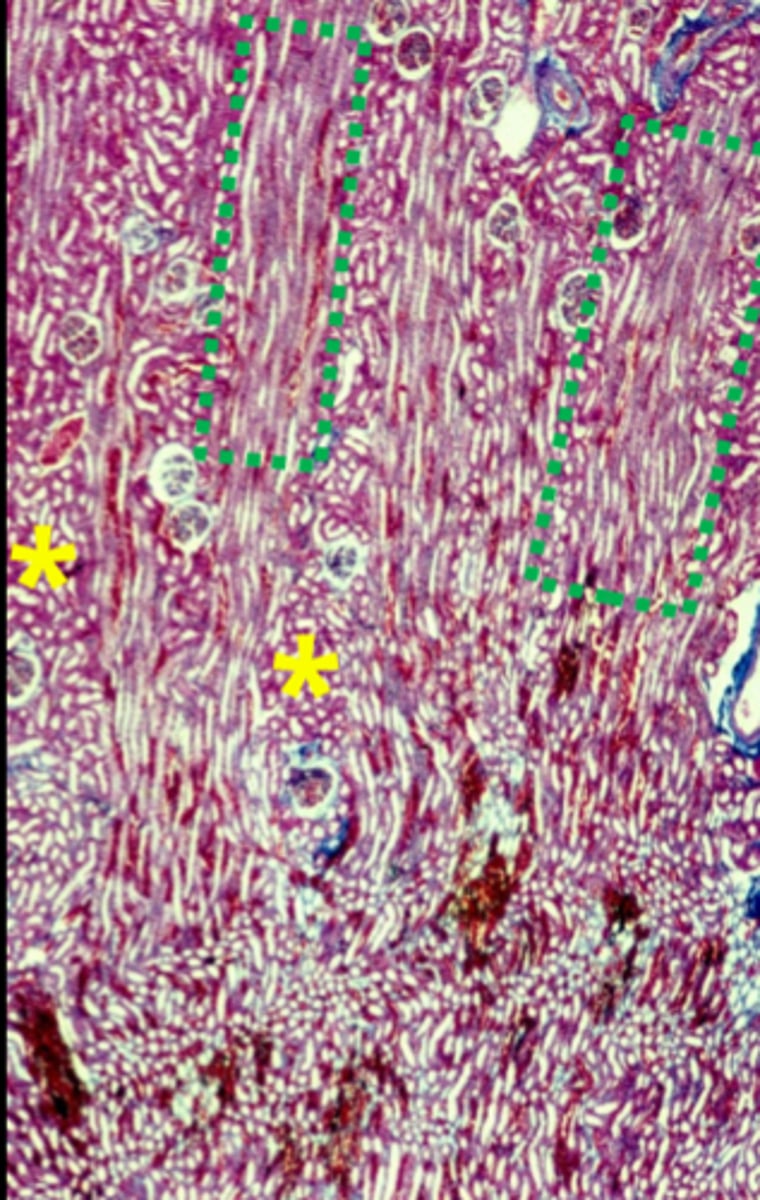

two types of structure in the cortex

medullary rays

cortical labyrinth

what is in the cortical labyrinth

straight tubules and collecting ducts (green boxes)

what is in the cortical labyrinth 4

convoluted tubules, and glomeruli

what is in the medullary rays 2

renal corpuscles,

irregular sections of the PCT,DCT

distal thick ascending limb

initial collecting tubule portion

the medullary rays are only in the ___________ of the kidney

proximal and distal straight tubules

arched collecting tubules and straight collecting tubules